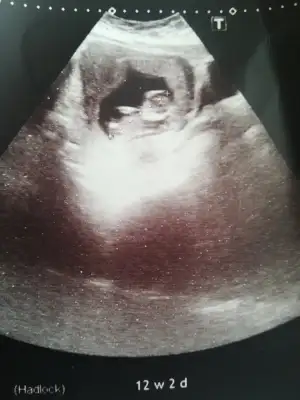

Burda 11 haftalikti bu aradaBu usg kaç hafta burdada nubu ne dik nede paralel yani pozisyonla alakalı oluyor böyle usgler beni yanıtabiliyor ama hemen kafa şeklini yazarımkafa şeklinede erkek yazmışım

Başka usg varmı net degil erkek gibi geldi bana eminde olamadım12+2 ama yüzü donukmus tahmin varmi